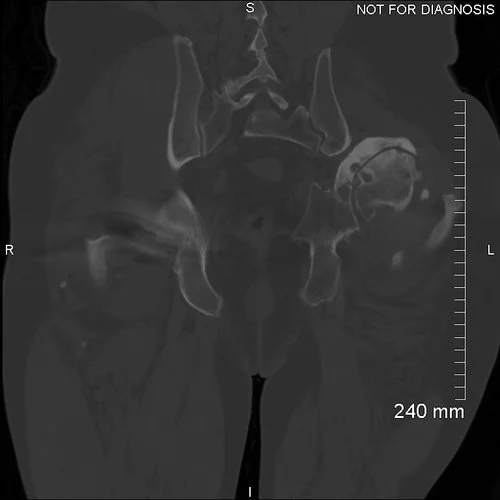

Coronal CT - showing a significantly abnormal left acetabulum with postero-superior dislocation of the left femoral head leading the neo-acetabular formation at the posterior of the left iliac blade. The neo-acetabulum is retroverted by 22 degrees. This was used to design the custom acetabular implant.

3D CT reconstruction showing the hemipelvic defect.